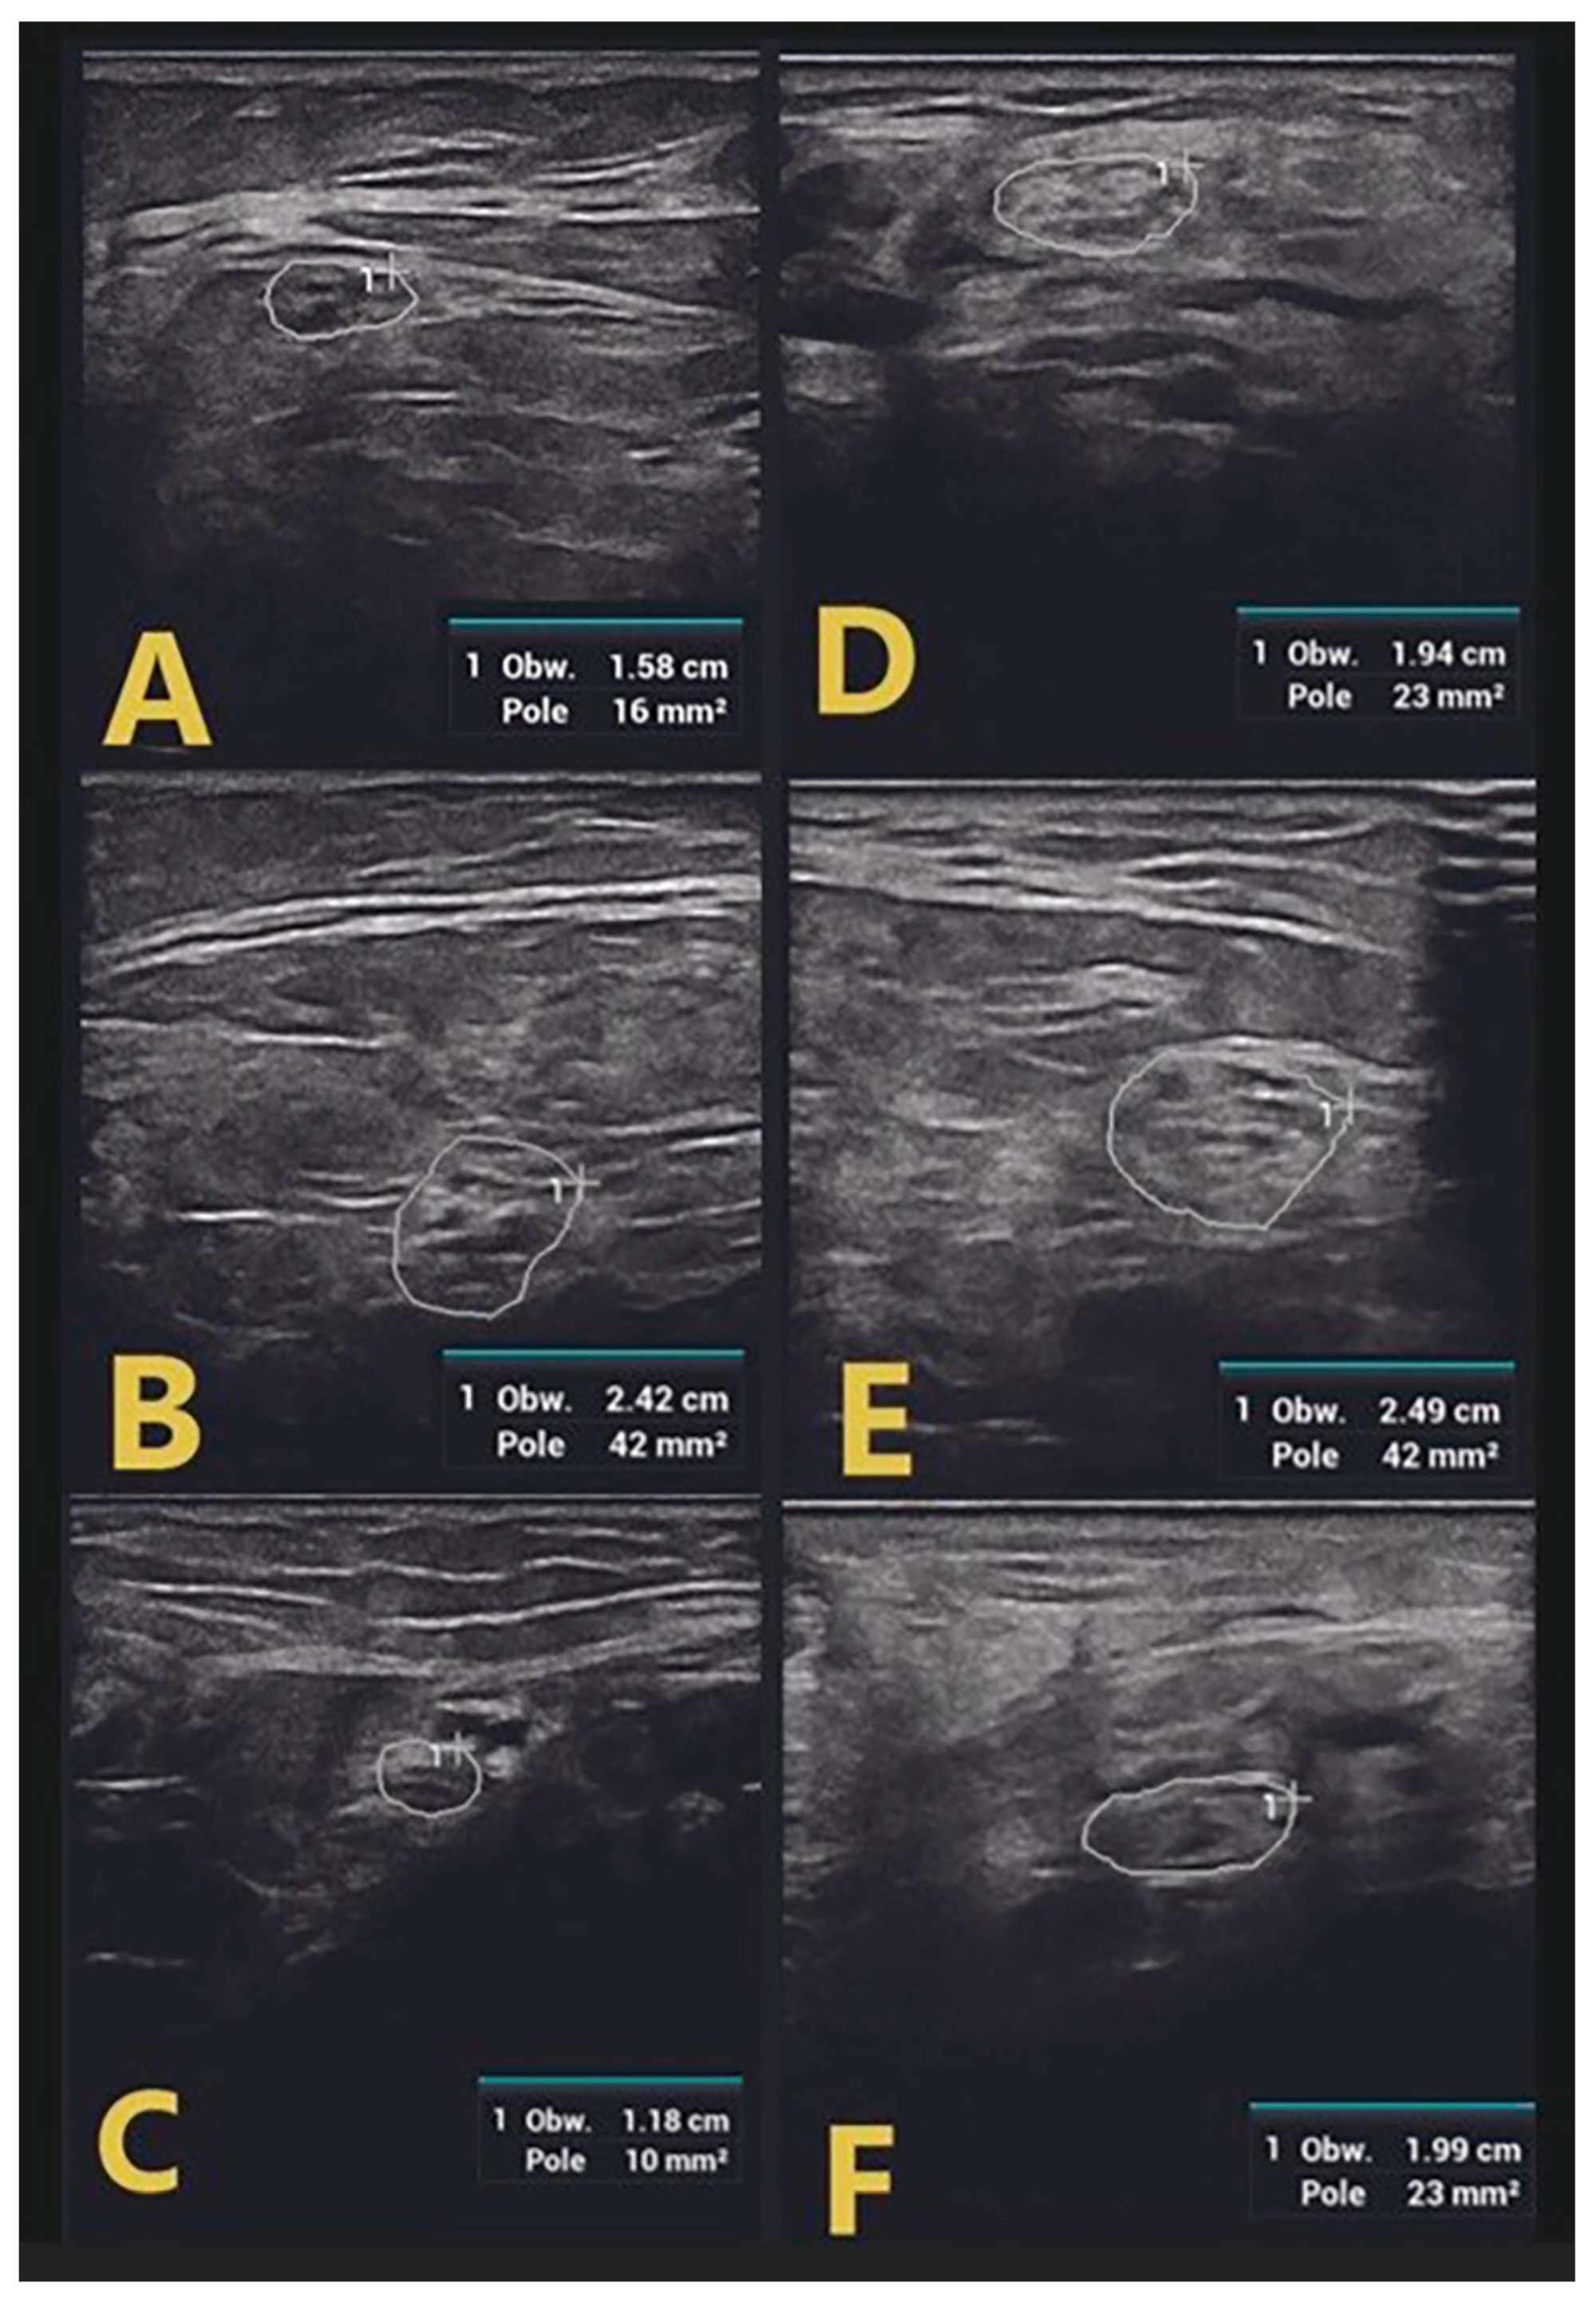

| SM | >6 months | - | 3/5 (ataxia) | ↑ CSA RMN, RUN, SBRRN ↑ C5 LAX CSA ↑↑ C6 | ↑↑ CSA RTN, RPN, ↑ CSA RSN | ↑ duration LMR | ↑ duration RMP |

| LAX CSA ↑ CSA VN | |||||||

| DJ | 17 months | - | 3/5 | ↑↑ CSA LMN ↑ CSA LUN ↑ C5 LAX CSA ↑↑ C6 LAX CSA ↑ CSA VN | ↑↑ CSA LTN, LPN, ↑ CSA LSN | ↑ duration LMM | ↑F latency LMT |

| DR | 6 months | - | 3/5 | ↑↑ CSA RMN ↑ CSA RUN ↑ C5 LAX CSA ↑↑ C6 LAX CSA ↑ CSA VN | ↑ CSA RTN, RPN, RSN | ↑ F latency RMT, LMT | |

| SZ | >5 months | - | 2/5 | ↑ CSA RMN, RUN ↑ C5 LAX CSA ↑↑ C6 LAX CSA ↑ CSA VN | ↑↑ CSA RTN, RPN, RSN | F wave absence RMT, LMP | |

| WJ | 17 months | - | 3/5 | ↑↑ CSA RMN ↑ C5 LAX CSA ↑↑ C6 LAX CSA ↑ CSA VN | ↑↑ CSA RTN, RPN, RSN | ↑ duration RMP, RMT | |

| BA | 6 months | 4/5 | 3/5 | ↑↑ CSA RMN, RUN ↑ C5 LAX CSA ↑↑ C6 LAX CSA ↑ CSA VN | ↑↑ CSA RTN, RPN, RSN | ↑ duration RMU | ↑ duration RMT |

| BD | 14 days | - | 2/5 | ↑ C5 LAX CSA ↑ C6 LAX CSA | ↑ CSA LTN, LPN | ↑ duration RMU, LMP | F-wave absence RMP |

| SMi | 4 days | 4/5 | 2/5 | ↑↑ CSA RMN ↑ C5 LAX CSA ↑ C6 LAX CSA | ↑ CSA RTN, | ↑ duration RMU | ↑F latency RMP, LMP ↑ duration RMP, LMP, RMT |

| LW | 6 weeks | - | 3/5 | ↑↑ CSA RMN, ↑ RUN ↑ C5 LAX CSA ↑ C6 LAX CSA | ↑ CSA RTN, RPN | ||